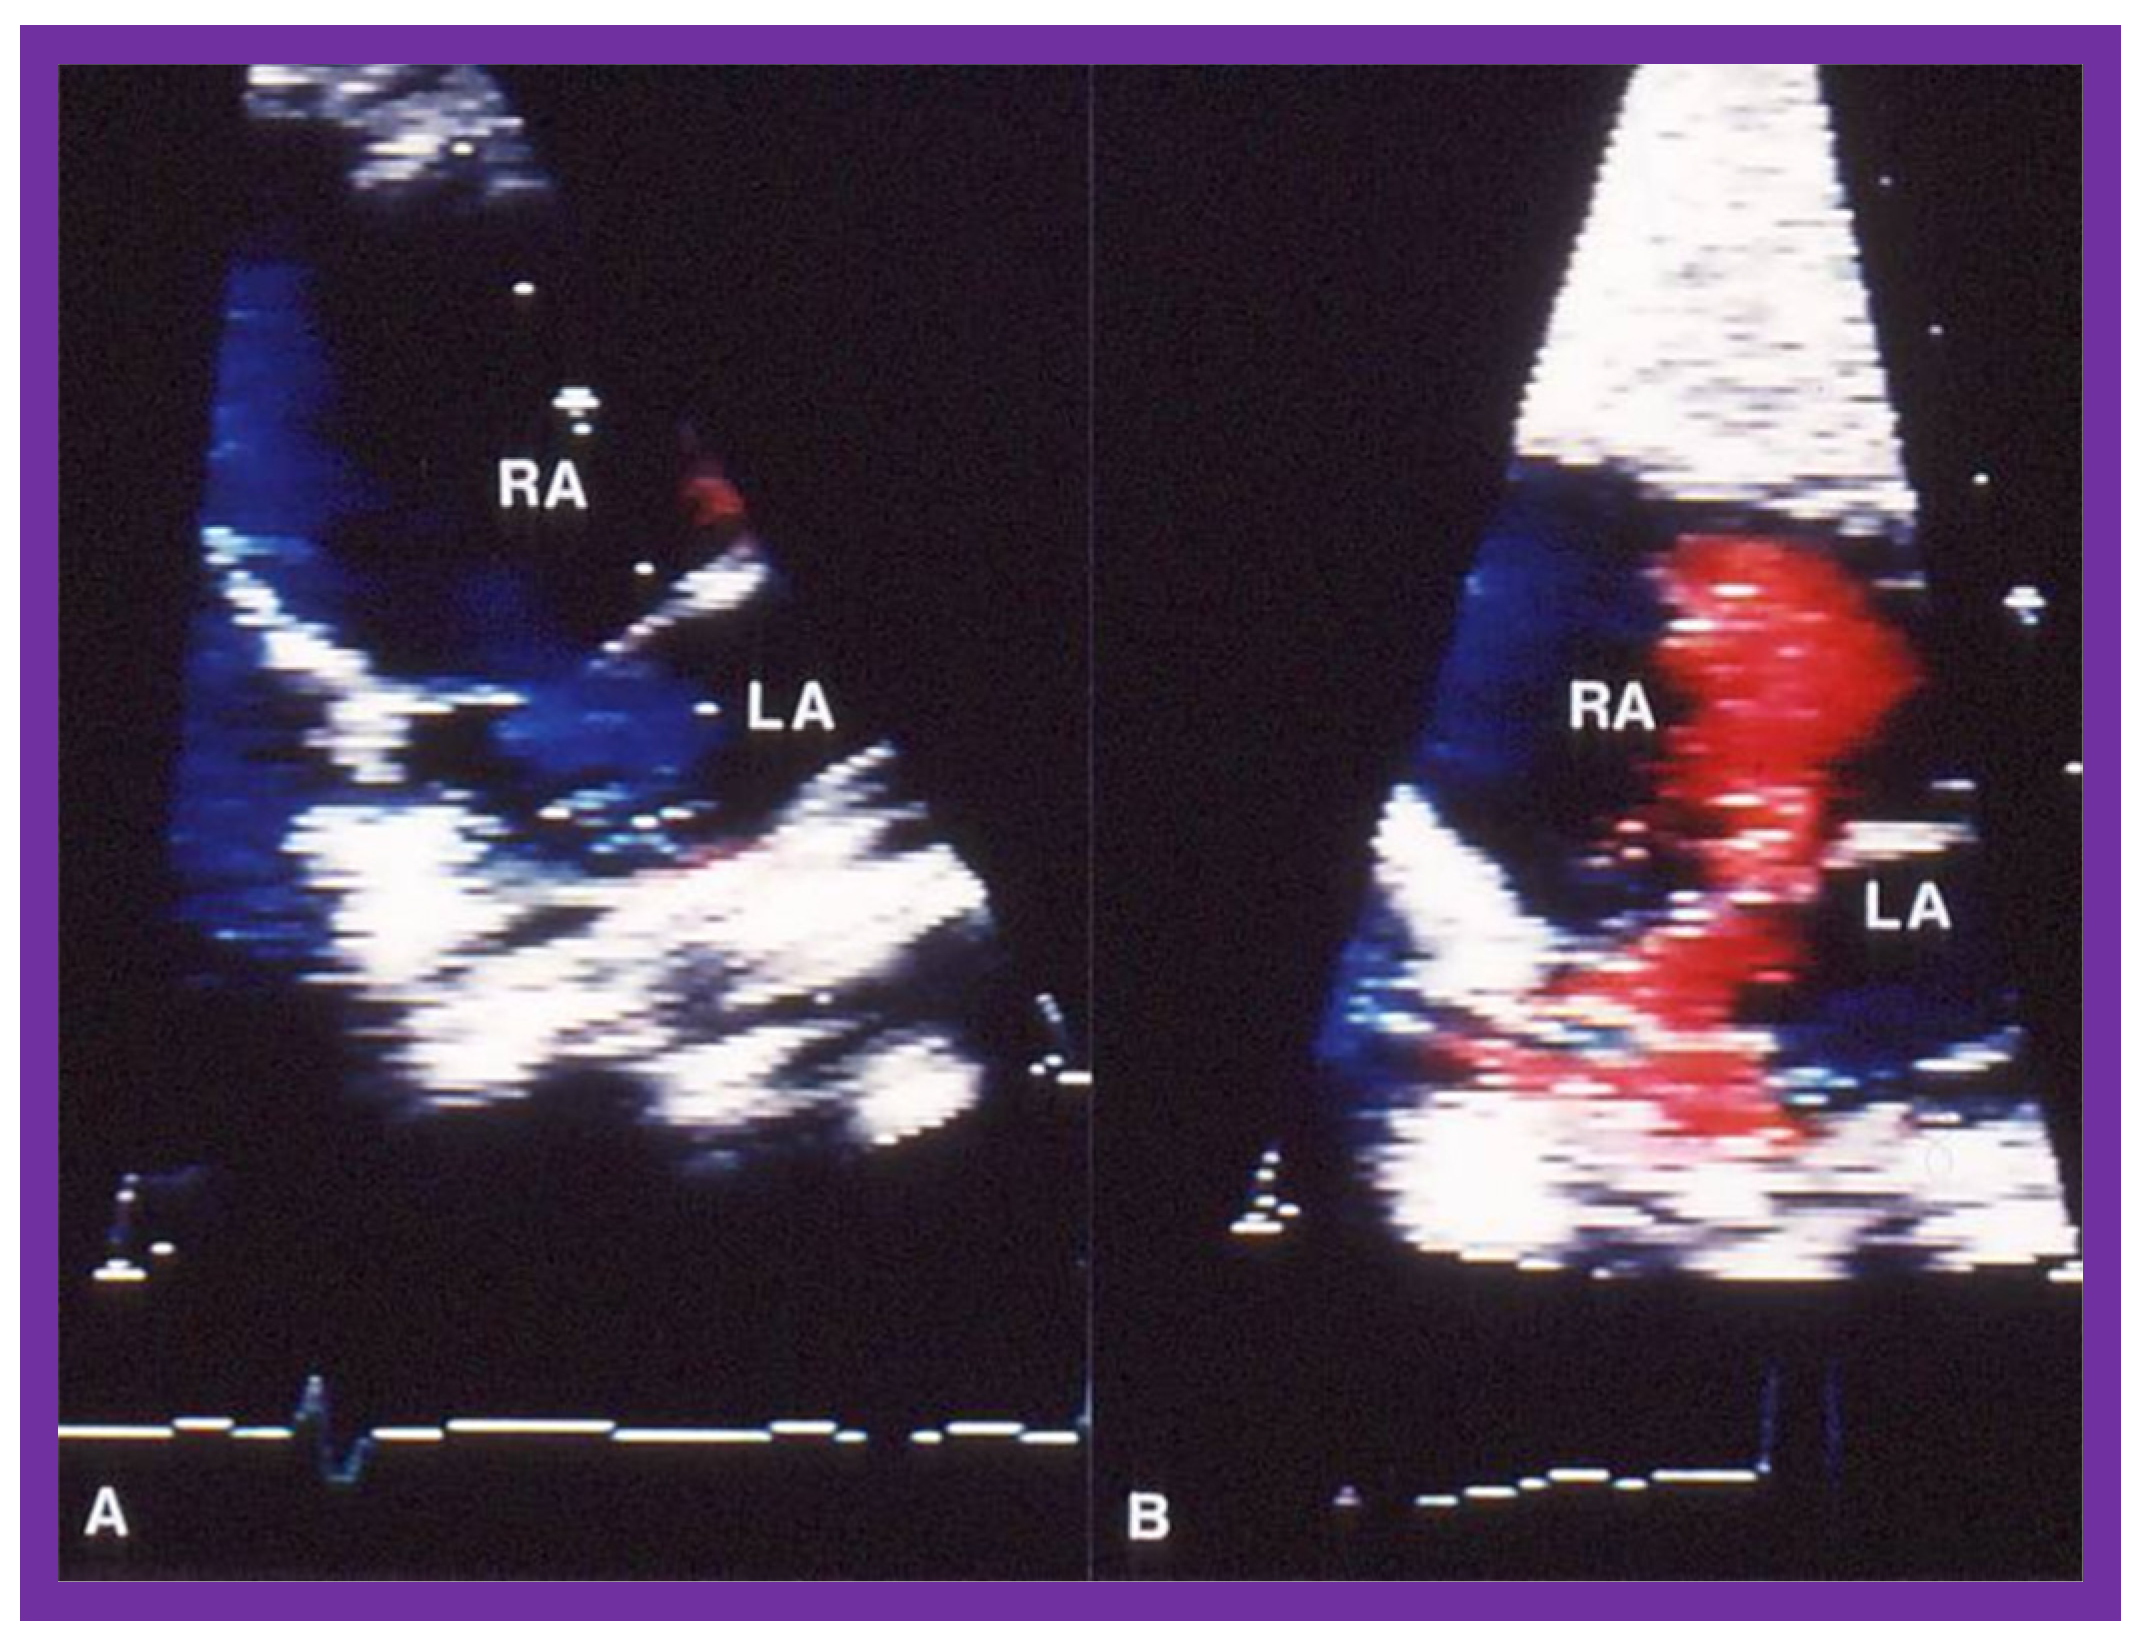

| 8. If angiographic (Figure 2A), pressure (Figure 1) and/or echo-Doppler (Figure 3B) data suggest, significant residual infundibular obstruction, beta blocker drug therapy may be necessary; we recommend it if the residual gradient is more than 50 mmHg [2,6]. |